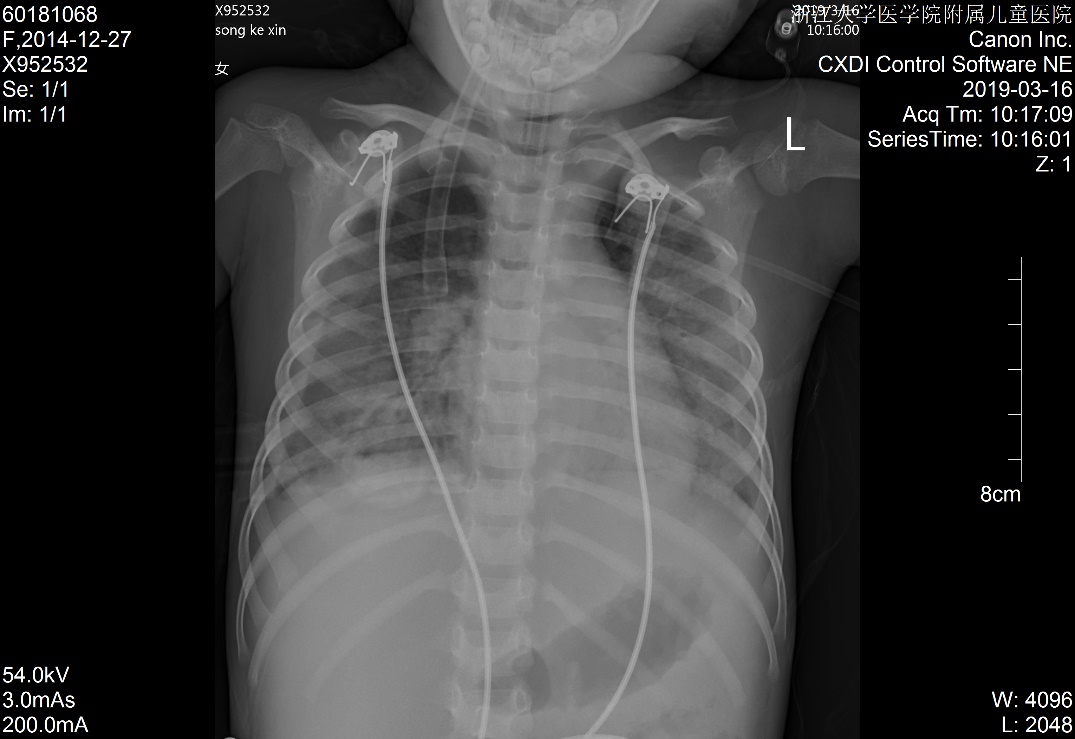

1 资料与方法患儿女,5岁2月,因“多尿、多饮、多食3个月余,意识不清1天余”由外院转入。3个月余前出现多尿、多饮、多食,家长未重视,未就诊。1 d前出现意识不清,并抽搐3次,急送当地医院就诊,当时查体情况具体不详,查血气电解质示pH 6.87,pCO225.9 mmHg,Na+ 125.4 mmol/L, Glu 17.1 mmol/L,Lac 1.1 mmol/L,HCO3- 4.6 mmol/L,ABE -28.1 mmol/L。考虑诊断“糖尿病、糖尿病酮症酸中毒、脑水肿?”收住当地医院。在当地医院住院期间,予大量补液[约3 L/24 h,大部分为晶体液,可能因为低血压,因住院期间曾使用多巴胺10 μg/(kg·min)维持],住院期间出现氧饱和度不能维持,遂予气管插管并机械辅助通气。因病情持续恶化,联系后转入本院PICU。既往史、个人史、出生史无殊。爷爷及外婆有糖尿病及高血压病。入院查体:T 37.8℃,脉搏:146次/min,呼吸:38次/min(为机械通气),血压98/77 mmHg(1 mmHg=0.133 kPa),无特殊面容及畸形,体质量:11 kg,气管插管带入,经皮血氧饱和度95%,镇静状态,双侧瞳孔等大等圆,直径2 mm,对光反射存在,颈软,余神经系统无明显阳性体征,面色苍白,消瘦貌,双肺呼吸音粗,可闻及湿啰音,腹软,肝脾肋下未及,皮肤弹性略差,肢端凉,毛细血管充盈时间5 s。入院后查白细胞计数8.52×109/ L-1,淋巴细胞15.4%,中性粒细胞82.0%,超敏C反应蛋白17.33 mg/L;血气分析:pH 6.996,pO2 91 mmHg, pCO2 43.5 mmHg,Na+ 126 mmol/L,Glu 21.0 mmol/L,Lac 2.9 mmol/ L,HCO3- 10.1 mmol/L,ABE -20.6 mmol/L;血氨63 μmol/ L;生化五类:总蛋白34.9 g/L,白蛋白26.5 g/L,丙氨酸氨基转移酶24 U/L,天门冬氨酸氨基转移酶96 U/L,肌酐147 μmol/L,尿素12.38 mmol/L,肌酸激酶1 680 U/L,肌酸激酶-MB活性166 U/L,甘油三酯6.05 mmol/L,胆固醇6.11 mmol/L,淀粉酶3 094.5 U/L;尿常规:尿酮体++,尿蛋白++,尿糖++++,尿隐血+++;糖化血红蛋白16.5%;血清C肽测定:0.116 nmol/L;糖尿病自身抗体阳性;脑脊液常规、生化及培养无殊;血尿培养阴性;胸片:两肺弥漫性病变,双侧胸腔积液,肺水肿待排(图 1);心超:左室收缩功能稍减低(EF 0.53),少量心包积液,二、三尖瓣轻度反流;腹部B超:肝大、腹腔积液。考虑诊断“急性呼吸窘迫综合征、急性肾功能损伤、1型糖尿病、糖尿病酮症酸中毒、脑水肿、多浆膜腔积液”,予呼吸机支持[HFO模式,FiO2:85%,f:5.8 HZ,ΔP:36 cmH2O(1 cmH2O=0.1 kPa),MAP:25 cmH2O, OI:23)、多巴胺及肾上腺素泵注维持血压、甘露醇降颅压、胰岛素注射降血糖及其他对症支持治疗,患儿入院第3天酮症酸中毒基本纠正,第6天改无创通气(CPAP,Flow:10 L/min,PEEP:4 cmH2O),入院第10天改大气吸入,复查胸片基本好转(图 2),住院期间未再抽搐,在停呼吸机机械通气镇静后意识好转,但较激惹、躁动,肾功能逐步恢复,住院28 d后出院,出院前患儿意识清,能完成日常对答,查头颅MRI提示脑萎缩改变,复查肺部影像学未出现遗留性病变,复查心超未见心包积液。现规律随访近一年,胰岛素治疗血糖控制尚可,未遗留明显神经系统、呼吸系统等后遗症。本研究经浙江大学医学院附属儿童医院伦理委员会批准(批准号:2020-IRB-078),并经患儿家属知情同意。

| 图 2 入院第10天胸片 |